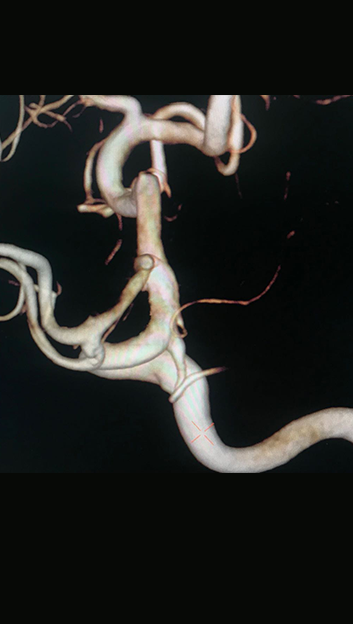

随访影像

术后一月复查的影像,动脉瘤未见复发及残留,载瘤动脉修复满意。